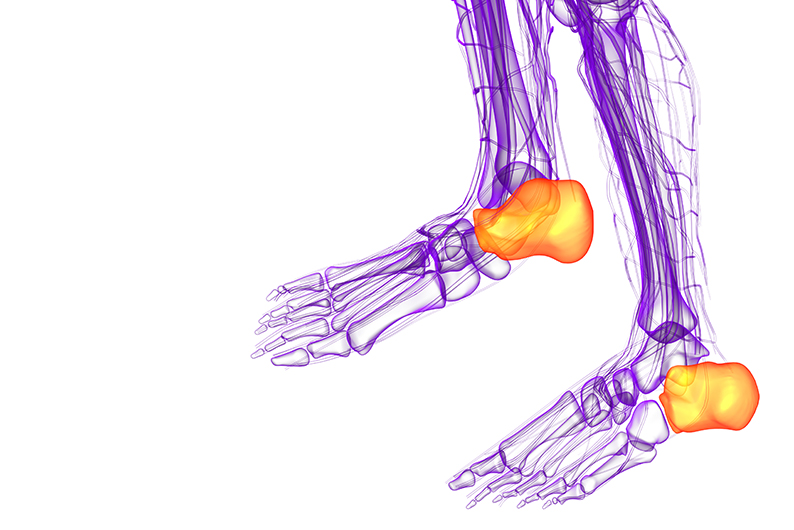

아킬레스건염

- 아킬레스건의 염증으로 인해 발생하는 통증으로, 발뒤꿈치와 발바닥 사이의 연결 부위에 통증이 느껴질 수 있습니다. 주로 격렬한 운동 후, 혹은 운동 부족 후 갑자기 운동을 시작할 때 자주 발생합니다. 통증은 특히 아침에 일어났을 때나 활동을 시작할 때 더 심해질 수 있습니다.